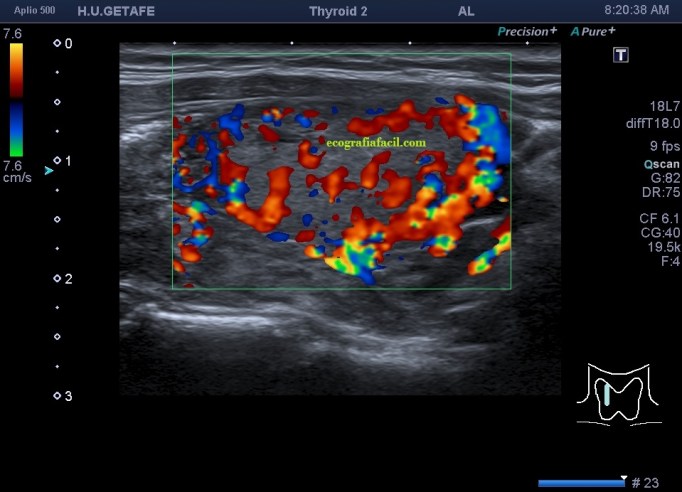

De la imagen 1 a 7 el protocolo habitual, el estudio particular del nódulo con medidas y aplicación del doppler demuestra el aspecto típico del Caballero Blanco.

De la 8 a la 11 estudio con Doppler.

La imagen 12 y 13 están adquiridas con una sonda de 18 Mhz.

- Doppler Color y Doppler Power aumentado de tamaño en el nódulo